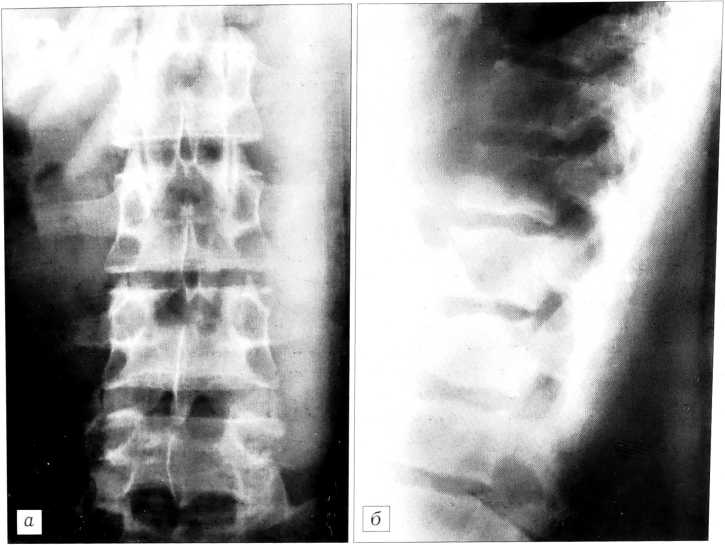

Симметричная гиперплазия суставных отростков обнаруживалась примерно с такой же частотой (132 пациента — 52,8%), причем преимущественно в «скомпрометированных» позвоночных сегментах. Мы не можем достоверно судить о врожденном характере данного вида дисплазии, так как гиперпластическая деформация задних отделов позвонков (утолщение и укорочение дуг, утолщение ножек дуг и суставных отростков), выявляемая почти исключительно в позвоночных сегментах с признаками остеохондропатии, свидетельствует о постоянной компенсаторной структурной перестройке сегмента (рис. 4). Отметим также, что увеличение размеров суставных отростков, особенно сегментарное, указывает на сужение позвоночного канала.

Рис. 4. Гиперпластическая деформация суставных отростков и дуг позвонков в L1- L2, L2—L3 позвоночных сегментах с признаками остеохондропатии в виде клиновидной деформации тел позвонков и грыж Шморля.